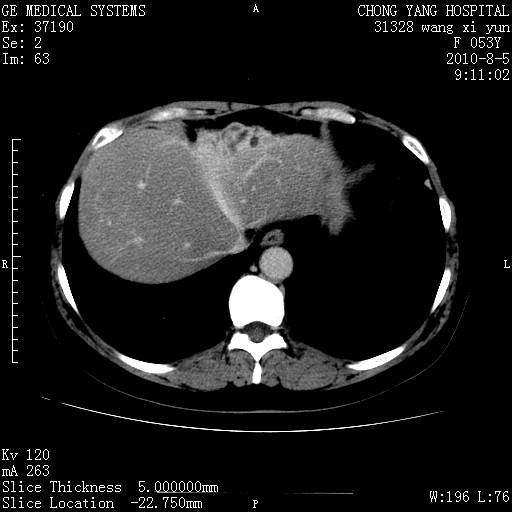

标题: CT28214:F41Y 血尿二十天,建议盆腔平扫加增强。

胆管细胞ca?

1)考虑肝左叶胆管细胞癌。2)脂肪肝。

支持胆管细胞ca。